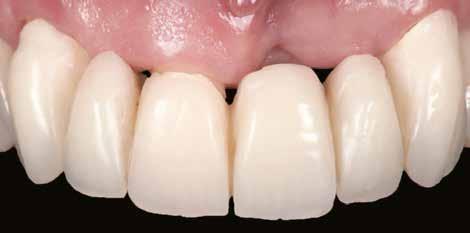

A végleges protetikai ellátást három hónappal az implantációt követően kezdtük meg. Az implantátumok gyógyulása panasz- és tünetmentes volt. Hagyományos, zárt kanalas A-szilikon lenyomatot vettünk (8. a–c ábrák). Egy esetben a gingivális emergenciát sikerült nagy pontossággal lemintázni fényre kötő folyékony kompozit segítségével (Master Flow, Biodinamica; 9. a–c ábrák). Három lítium-diszilikát és egy monolitikus cirkonkorona készült (10. a–b. ábrák), amelyek cementtel rögzültek a végleges protetikai fejeken (Dual RelyX™ U200, 3M; 11. a–b ábrák).

10. a ábra: Végleges lítium-diszilikát koronák. – 10. b ábra: Végleges monolitikus cirkónium-dioxid korona. – 11. a–b ábrák: Klinikai megjelenés tizenkét hónap elteltével. 12. a–b ábrák: Tizenkét hónapos kontrollröntgen-felvételek.